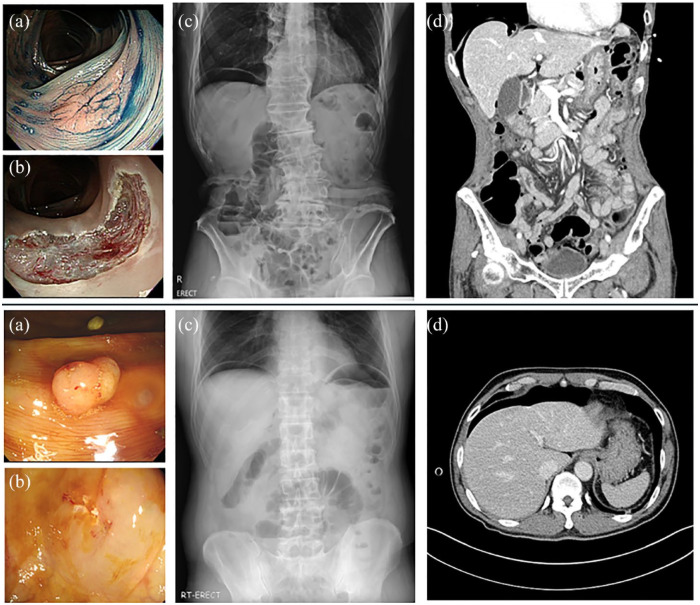

Results: Microperforations occurred in 12 patients (8 males; age: median 64.5 years). Polyps with microperforations were more frequent in the right colon (83.3% vs 33.3%). Endoscopic mucosal resection with precutting (EMR-P; 16.7% vs 0.0%) or hot-snare polypectomy (8.3% vs 0.0%) was more frequently performed in the microperforation group. Muscle fibers at the polypectomy site were more frequently visible in the microperforation group (58.3% vs 8.3%). By multivariate analysis, right colon location and visible muscle fibers were independent risk factors for microperforation. All patients with microperforation received intravenous antibiotics and were advised to fast. Patients responded well to these conservative treatments and were discharged after a median of 3 (2-6.75) days of hospital stay.

Conclusion: Our data suggest that conservative treatment is feasible and could be the primary management option for selected patients with microperforations postcolonoscopic polypectomy. Right-sided colonic polyps and visible muscle fibers predispose to microperforations.